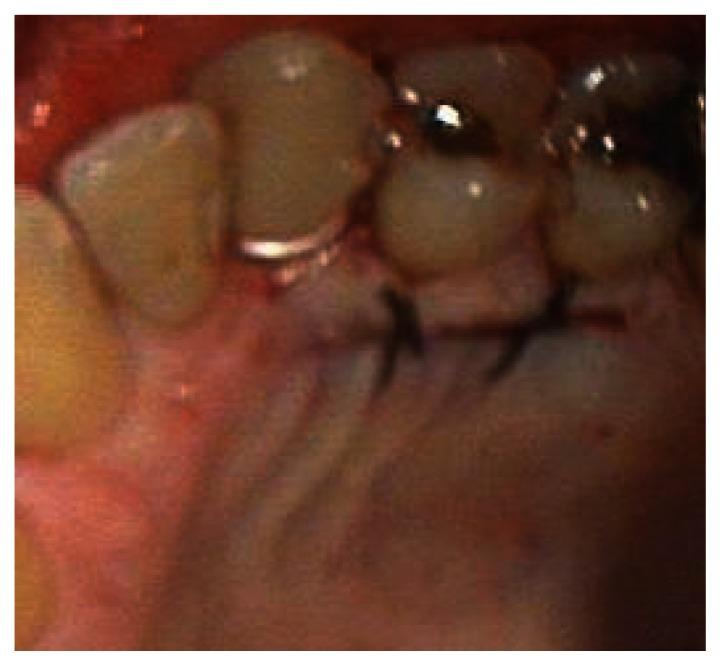

This case report describes the treatment of a maxillary canine that had 4 mm of marginal gingival recession. The exposed root had been previously restored with a composite class 5 restoration. The restoration was removed and the root planed and demineralized. The root was then covered by a subepithelial connective tissue graft harvested from the palate. The flap was coronally positioned to completely cover the graft and exposed root. The healing was photographed post-operatively at one month, six months, and seven years. Root coverage increased to 100% after seven years. The zone of attached gingiva also increased.